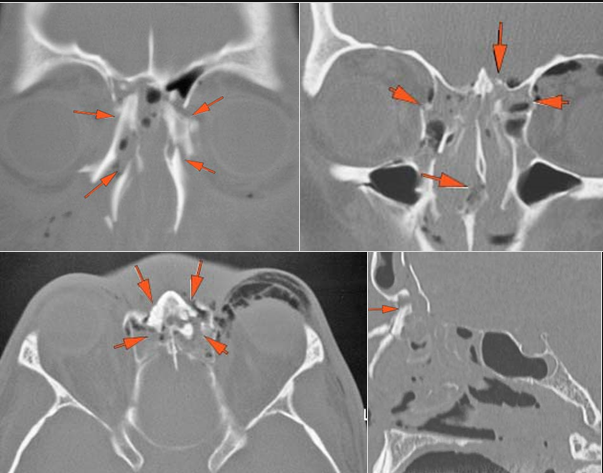

The medial, lateral and posterior maxillary walls are fractured. |

Yes | NA |

The infraorbital rims and orbital process of the zygoma and/or frontozygomatic suture are fractured. |

The pterygoid processes of the sphenoid bone are fractured. |

The mesial naso-orbito-ethmoid complex is fractured. Specifically, there is bony injury of the nasal bones or the frontal process of the maxilla and the medial walls of the orbit are abnormal. |

There is injury of the ethmoid complex. Specifically, the ethmoid roof, olfactory fossa and the cribriform plate are fractured and/or significantly dehiscent. |

The the zygomatic arch, frontozygomatic suture or infraorbital rim are fractured. |

The lateral wall of the orbit is fractured. |

The circumferential extraconal and the intraconal orbital fat are edematous. |

The extraocular muscles are swollen. |

Proptosis is present. |

There is evident general optic sheath swelling or swelling at the junction of the globe and sheath to suggest an optic sheath hematoma. |

LeFort type III, orbital zygomatic and orbital floor and fronto - naso-ethmoidal complex fractures with possible injury optic nerve/sheath - extent described above.

Possible optic sheath hematoma - suggest the option of further consultation by the ophthalmology service.